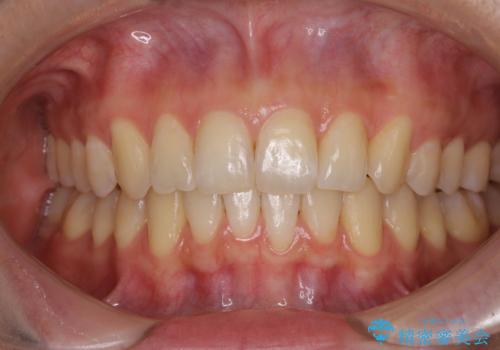

前歯のデコボコを改善 目立たないワイヤー矯正

- 前歯のデコボコを気にして来院された患者様です。

下顎が骨格的にずれており、上下正中を合わせることは難しいことが予想されたため、デコボコの解消を主目的として、ワイヤー矯正を行うこととしました。

治療途中で出産されたこともあり、当初予定よりも終了までに期間がかかってしまいました。

舌を前方に突出する癖があったため、上下前歯がなかなか接触しなかったことも治療期間が伸びた要因です。